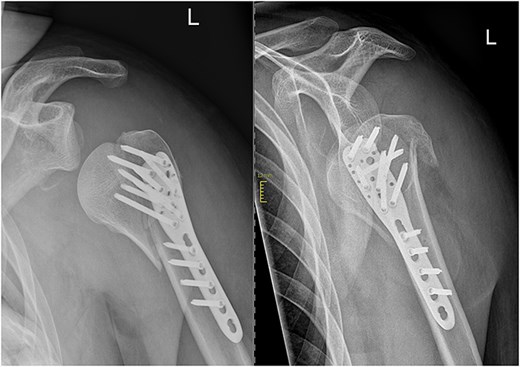

Open reduction and internal fixation with a locking plate was performed the following day. Following the deltopectoral approach, a reduction of the antero-inferiorly dislocated fragment through Kocher maneuvers and traction on the head fragment using a pointed reduction forceps were achieved. Subsequently, the head-split component was addressed by securing it with Ethibond sutures within the rotator cuff. The remaining fragments were then reduced and stabilized using a 5-hole anatomical locking compression plate along with a total of eight head and seven shaft screws, all performed under radiological guidance (Fig. 2).